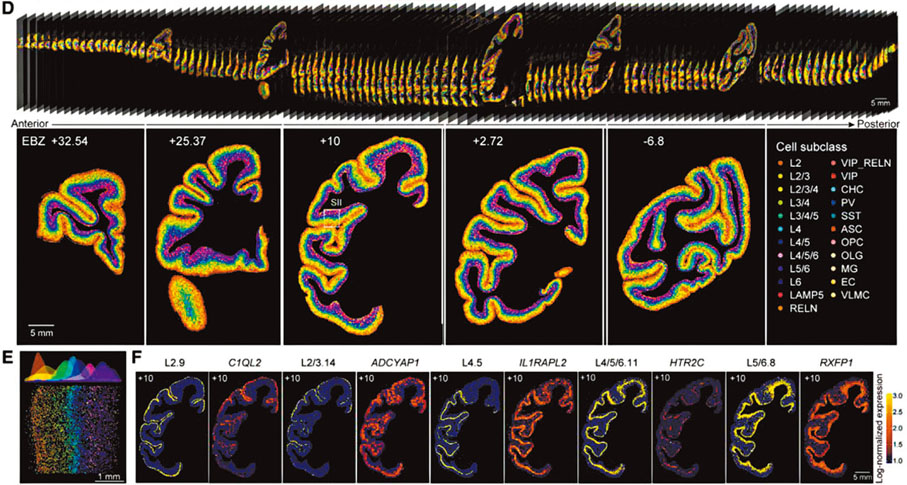

◆ 獼猴大腦皮層細胞類型空間分布圖譜。香港文匯報深圳傳真

世界首套單細胞分辨率的獼猴大腦皮層細胞空間分布圖譜誕生,該圖譜被稱為獼猴大腦皮層細胞三維「地圖」。這使科學家們能夠清楚地知道,獼猴大腦皮層細胞類型及其分布位置,奠定了阿爾茲海默病、帕金森病等腦疾病研究新基礎。作為目前最完整的靈長類腦細胞「說明書」,該研究還能為人腦功能、腦疾病、腦機接口等腦科學領域研究的基礎認知提供參考,大幅加快腦科學研究進程。 7月12日,國際學術期刊《Cell》在線發表了這一由中國科學家們領銜的重要突破。◆香港文匯報記者 郭若溪 深圳報道

文章共同通訊作者、中國科學院腦科學與智能技術卓越創新中心研究員李澄宇表示,此次研究通過對獼猴大腦皮層的143個腦區中單個細胞基因表達及狀態、空間信息進行聯合分析,成功繪製出獼猴大腦皮層細胞類型分類樹,揭示了細胞類型組成和靈長類腦區層級結構之間的關係,為進一步研究各類神經元之間的鏈接提供了基礎。

中國科學院腦智卓越中心全腦介觀神經聯接圖譜研究(單細胞分型)平台主任李超介紹,團隊檢測了4,000多萬個皮層細胞,根據細胞分子及空間分布規律,將之分為264種不同的細胞類型。

研究表明,獼猴大腦中大量興奮性神經元、抑制性神經元以及非神經元細胞在大腦皮層中的分布呈現明顯的各層面及各腦區的特異性。研究團隊以視覺系統和軀體感覺系統為例,展開進一步研究,發現兩個系統的細胞類型組成與腦區層級組織之間存在顯著的相關性。更有趣的是,處於相同層級的腦區,往往細胞類型組成類似,揭示了細胞組成和腦區結構之間的關係。